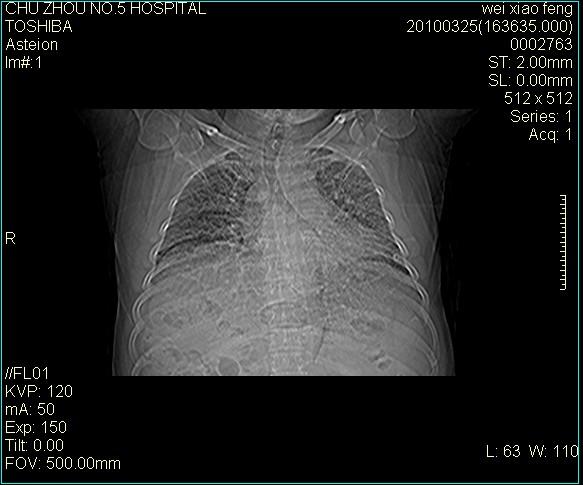

男,60岁,反复咳、痰、喘3月,加重3天。

双肺间质性改变。

考虑双肺血型潘散肺结核/

间质性肺炎伴间质纤维化!不排除伴有职业病!

双肺间质纤维化,双肺血型潘散肺结核。